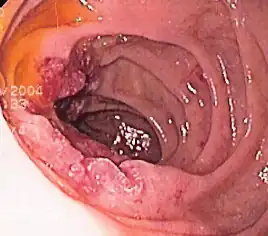

Гастроинтестинальная эндоскопия

Эндоскопические исследования выполняются с помощью специальных аппаратов-эндоскопов, вводимых пациенту через естественные отверстия — рот или задний проход и передающих изображение в исследуемом органе или на окуляр эндоскопа или на монитор. В современной практике используются два типа гибких эндоскопов: волоконно-оптические фиброэндоскопы и видеоэндоскопы, оцифровывающие видимую в объектив картинку и передающие её в таком виде на монитор или окуляр. Эзофаго-, гастро-, дуодено- и/или еюноскопия показаны при подозрении на воспаление или язву, а также другие заболевания пищевода, желудка, тонкой кишки, фатерова сосочка. Колоноскопия — эндоскопическое исследование толстой кишки, показана при наличии клинических признаков, указывающих на поражение толстой кишки, наблюдении за пациентом в процессе лечения, при осмотрах, направленных на выявление на ранней стадии онкологических и других заболеваний[22].

Гибкий волоконно-оптический фиброэндоскоп Эндоскопия пищевода пациента с варикозным расширением вен пищевода

Дуоденоскопия пациента с аденокарциномой двенадцатиперстной кишки